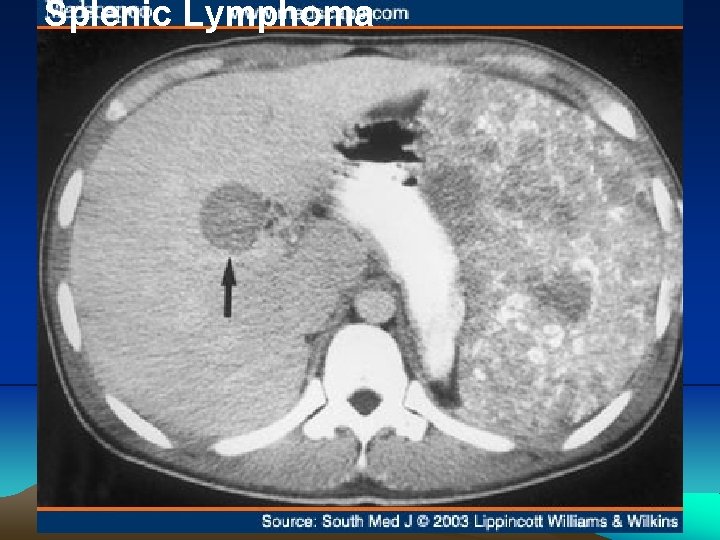

Splenic Lymphoma